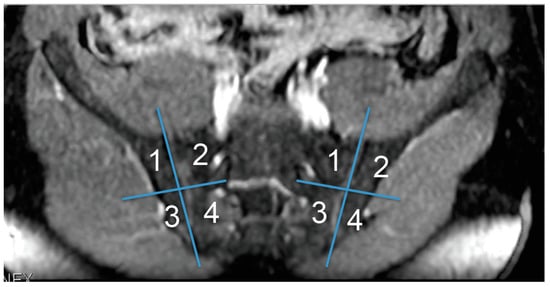

Figure 2. (ac). SI in a 42 year-old woman with “active” Crohn’s disease. A single shot fast spin echo breath hold (SSFSE BH) ASSET T2w sequence in the coronal plane showed subchondral bone marrow edema on both the sacral and iliac aspects of the left SIJ (arrows in (a)) corresponding to erosions (arrows in (b)) on the post-contrast LAVA sequence. Erosions were also detected on the sacral aspect of the right SIJ (arrowhead in (b)). A subsequent dedicated MRI protocol (c) confirmed bilateral SI.